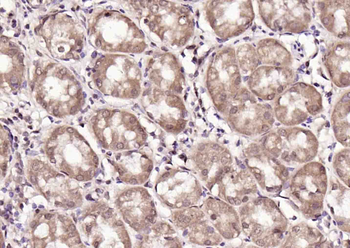

100 μl, 50 μl, 200 μl - HSC70 Mouse Monoclonal Antibody [orb704174]Featured

IF, IHC-Fr, IHC-P, WB

Human, Mouse, Rat

Mouse, Rat

Mouse

Monoclonal

Unconjugated

100 μl, 50 μl, 200 μl - ATF4 Recombinant Rabbit Monoclonal Antibody [orb704304]Featured